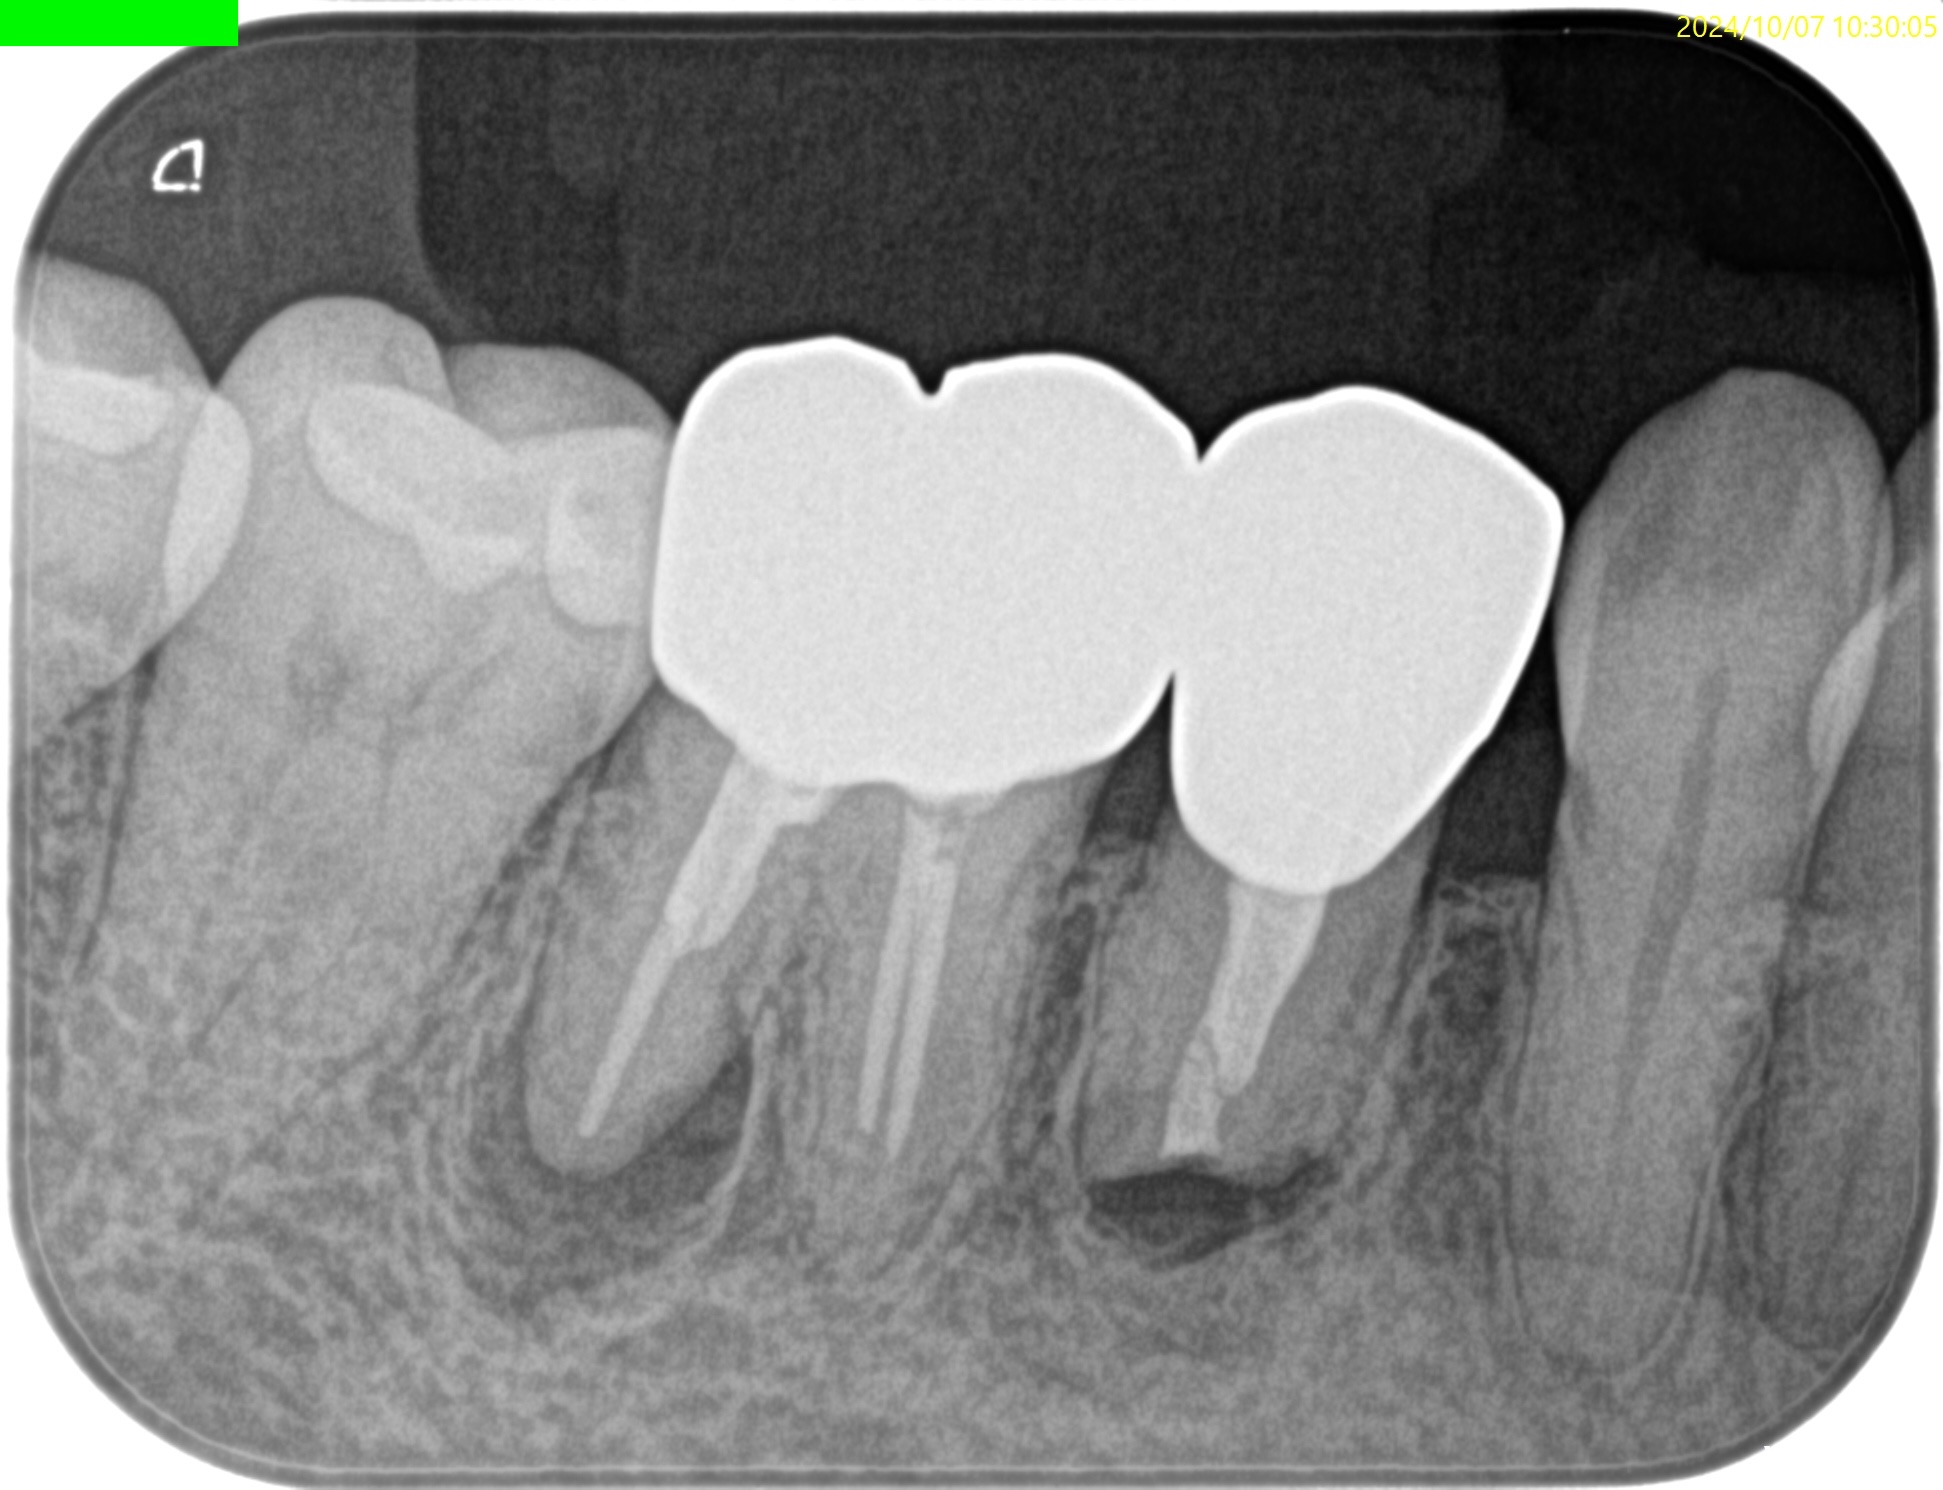

4年経過しても治癒していない。

が、患者さんは症状がないのでこのまま経過を見ることになった。